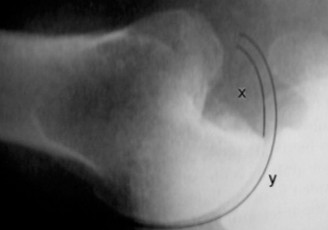

Physicians should obtain a complete set of x-rays. Special views include the modified Westpoint axillary (Fig. 2–43B) to evaluate for glenoid loss and the stryker notch view (Fig. 2–43A) to evaluate the Hill–Sachs lesion. This view brings the posterolateral defect into direct visualization. 3D CT imaging is also very useful for evaluating glenoid bone loss and estimating the size of the Hill–Sachs lesion.

--- _Figure 2–43_A: Stryker notch view. B: West point axillary view. (From Bucholz RW and Heckman JD. Rockwood and Green’s Fractures in Adults 7e. Philadelphia: Wolters Kluwer, 2009.)

Figure 2–47 The size of the humeral head defect can be calculated by dividing the arc of impaction (x) by the total articular surface arc (y).